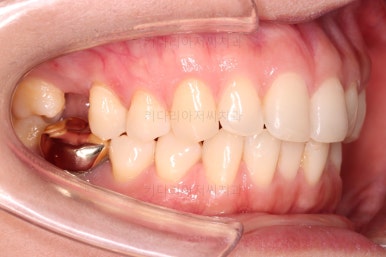

마찬가지로 부산치아교정비용 초진 시 입안의 모습입니다.

아랫니가 많이 보이지 않는 타입이라서 잘 몰랐는데 입안을 관찰해 보니 아래 앞니가 삐뚤어 있네요.

이 부분도 꼭 교정해야 될 정도는 아니여서 선택의 문제라고 할 수 있는데요.

어금니가 문제였습니다.

윗니 어금니가 하나 없는 상태였고요.

어금니가 없이 지낸지 꽤 시간이 흐른터라 뒤쪽 어금니가 앞으로 쓰러져 공간을 잠식하고 있었습니다.